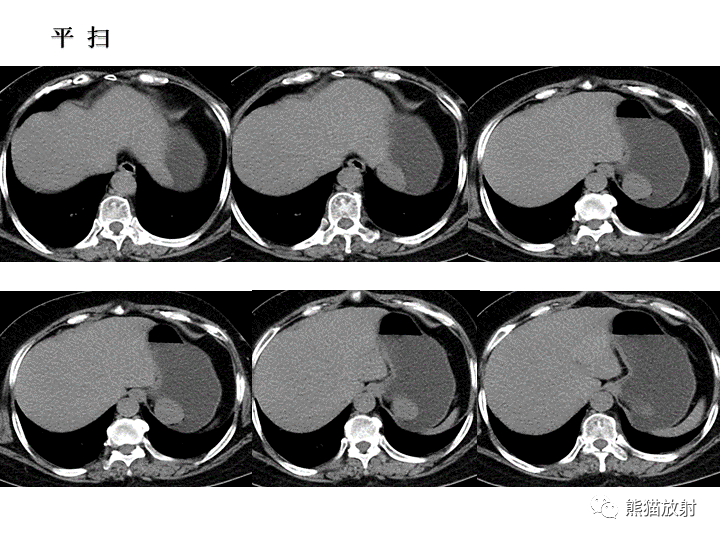

【病例】胃间质瘤VS神经鞘瘤-1